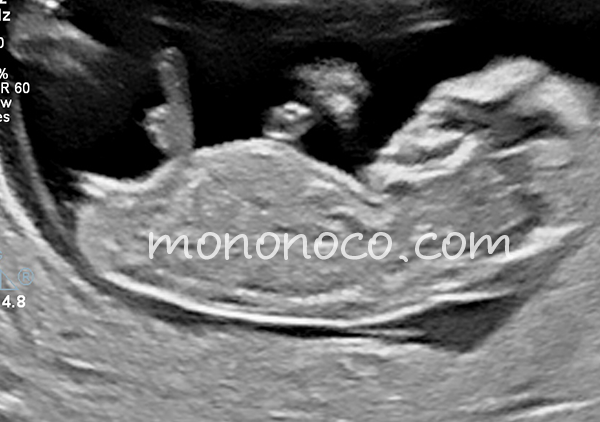

ちなみにいつものエコー画像バージョン。素人が判断とか難しすぎる…